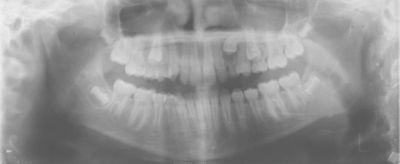

One case posted to the community involved a 13-year-old with a lingually displaced UL3 and plans for full braces, extraction of the primary ULc, and possible exposure and ligation (Figs. 1–5). The treating orthodontist asked: How likely is this canine to correct on its own after extraction?

Fig. 1